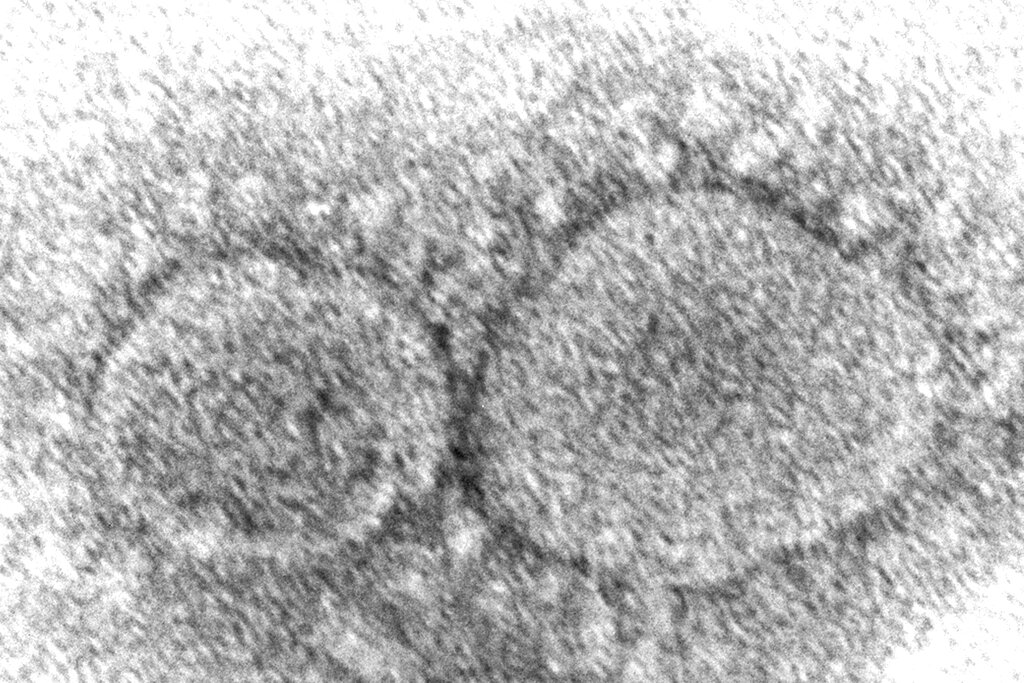

(AP) – The coronavirus mutant that is now dominant in the United States is a member of the omicron family but scientists say it spreads faster than its omicron predecessors, is adept at escaping immunity and might possibly cause more serious disease.

Why? Because it combines properties of both omicron and delta, the nation’s dominant variant in the middle of last year.